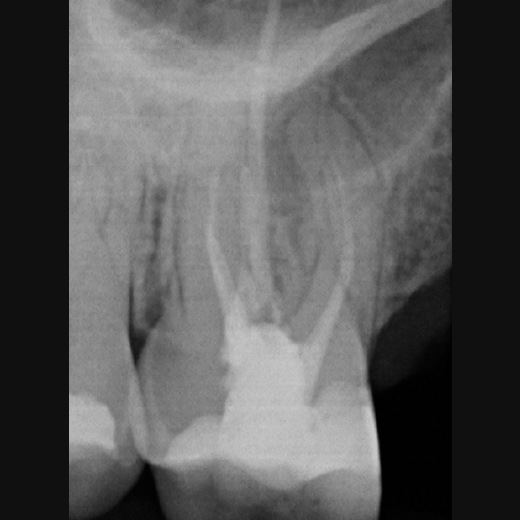

Fallbeispiel: Revision 45 nach Wurzelspitzenresektion (WSR) Recall 30 Monate

Auch Zähne, die bereits eine Wurzelspitzenresektion erhalten haben, können erfolgreich mit einer Revision behandelt werden.